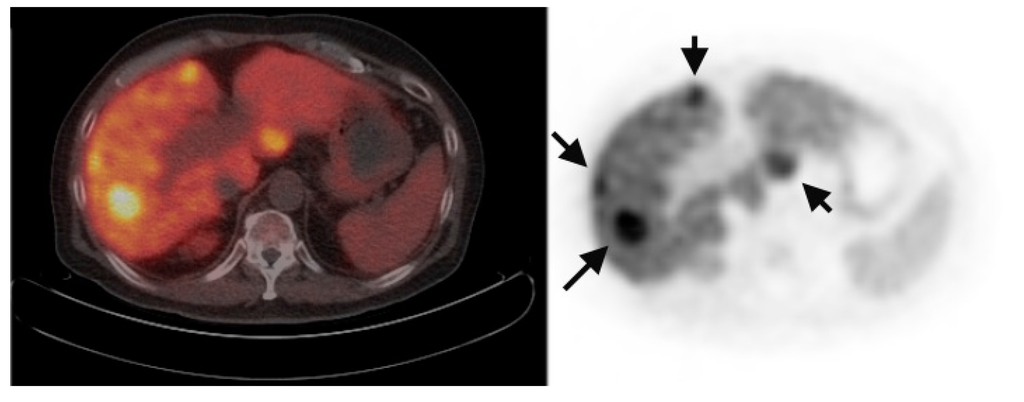

Multiple foci of increased FCh uptake in the liver consistent with multifocal or multinodular HCC (example, Figure 1) were noted in 8 of the 13 patients with increased primary tumor uptake. Of these, the areas of increased FCh uptake were adjacent to the treatment site (examples, Figure 2 and Figure 3) in 2 patients treated by local tumor ablation and 1 patient treated by liver resection. In one newly diagnosed case, PET demonstrated heterogeneous tumor FCh uptake with increased peripheral uptake and markedly diminished central uptake (Figure 4). Pathology in this case revealed a highly-necrotic tumor with Edmondson-Steiner grade 3 differentiation.

Figure 2.

Recurrent HCC surrounding previous radiofrequency ablation site. PET/CT (left) shows absent FCh uptake (white arrow) in an area of the liver where HCC was previously treated by radiofrequency ablation. Corresponding PET (right) clearly shows multiple foci of increased FCh uptake surrounding the ablation site consistent with recurrent HCC (arrows). A pulmonary metastasis was also detected in this patient (arrowheads).